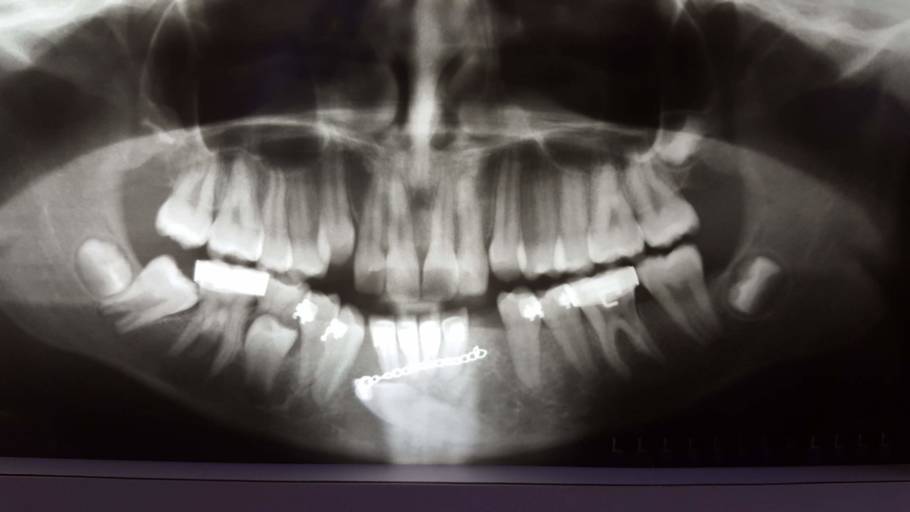

What are the chances of a tooth being rejected that has already received multiple restorations (over half is composite) after a root canal? I have an infection, and am receiving treatment. I have already taken one round of antibiotics, and start a second round tomorrow. I was told I could choose to do a root canal or extraction. I am trying to decide what would be in my best interest. The tooth in question has had multiple restorations, the most recent due to the tooth cracking and almost half of it falling out, therefor half composite. I have noticed that this tooth also moves slightly or is not as snug in the gums as the rest of my teeth. Since I have already spent $600-700 on this tooth my concern lies in spending the money for the canal and crown ... only to have it reject in a few months.

When a tooth has an infection, it tends to feel more mobile than your other teeth due to the inflammation and infections surrounding the tooth. Once the infection is under control and a root canal is completed, the ligaments surrounding the tooth with tighten back up. I can certainly understand your hesitation, however, most dentists' or Endodontists' will not perform a root canal if the tooth has a guarded prognosis. It will be imperative to have the crown placed immediately after the root canal in order to prevent any further fractures or trauma to the tooth. Always keep in mind, dental treatment is never guaranteed. The treatment is done with the best intentions, however you must responsible for your homecare and yearly dental x-rays in order to detect any recurrent or new dental caries. There is nothing better than your own teeth and extracting the tooth is a temporary fix, it must be restored with a dental implant or dental prosthesis such as a partial denture. Discuss your concerns with the treating dentist prior to starting treatment, in order to be sure you are making the best decision for your dental needs.